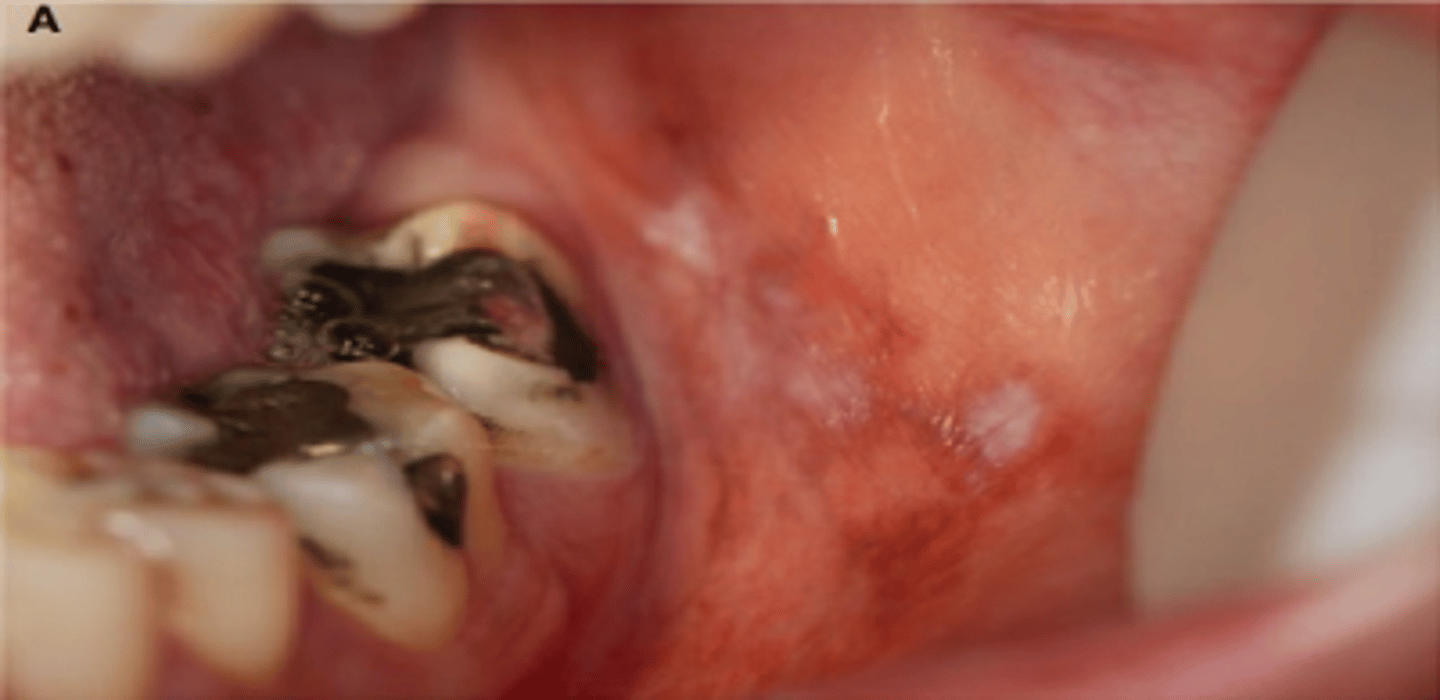

What are lichenoid lesions? (+ common locations)

similar to lichen planus - unilateral

⢠usually a drug rxn

⢠common locations: buccal mucosa, tongue (NOT GINGIVA!!!)